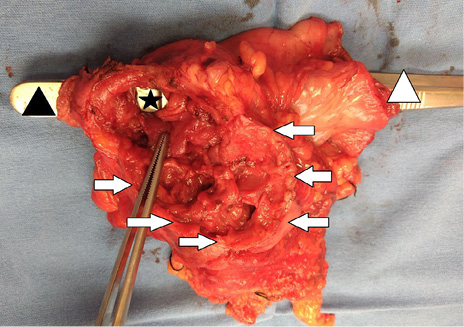

Previo consentimiento informado, se realiza laparotomía exploradora donde se encuentra un plastrón a nivel de vesícula biliar y primera porción de duodeno. Se realiza disección del área afectada encontrando una fístula colecistoduodenal con sangrado activo, se procede a realizar colecistectomía parcial (dejando la pared hepática de la vesícula biliar) más antrectomía y resección de primera porción del duodeno (Figura 2). Se deja clausurada la porción duodenal y antro gástrico, dejando una sonda de gastrostomía para la descompresión gástrica, empaquetamiento perihepático y abdomen en bolsa de Bogotá. La paciente pasa a la unidad de cuidados intensivos del adulto (UCI-A) para estabilización y mejora de condiciones. A las 36 horas del primer procedimiento se realiza una cirugía de revisión encontrando abdomen sin datos de sangrado remanente, se procede a realizar muñón de duodeno y estómago remanentes. Se revisa y perpetúa la sonda de gastrostomía para descompresión, se coloca una sonda de yeyunostomía para alimentación y se cierra la pared abdominal en masa. La paciente mejora condiciones y es egresada por mejoría de la UCI-A a los 7 días de estancia. En piso hospitalario, la paciente continúa con mejoría mientras es alimentada por sonda de yeyunostomía. A los 25 días postquirúrgicos es dada de alta hospitalaria por mejoría con visitas periódicas a la consulta externa.